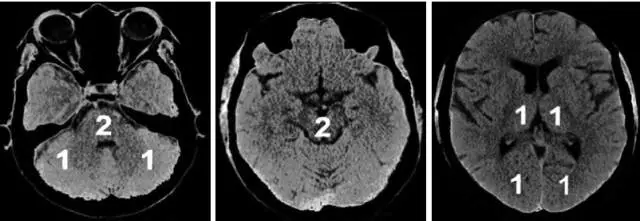

为评估后循环梗死患者早期梗死情况,PUETZ等[25]建立了评估后循环的AIS预后早期CT评分(posterior circulation Acute Stroke Prognosis Early CT score,pc-ASPECTS)。pc-ASPECTS总分也是10分:双侧丘脑和小脑各1分,双侧大脑后动脉供血区各1分,中脑和脑桥为2分(图2)。

图2. pc-ASPECTS评分中后循环供血区功能分区

注:pc-ASPECTS:后循环急性卒中预后早期计算机断层扫描评分